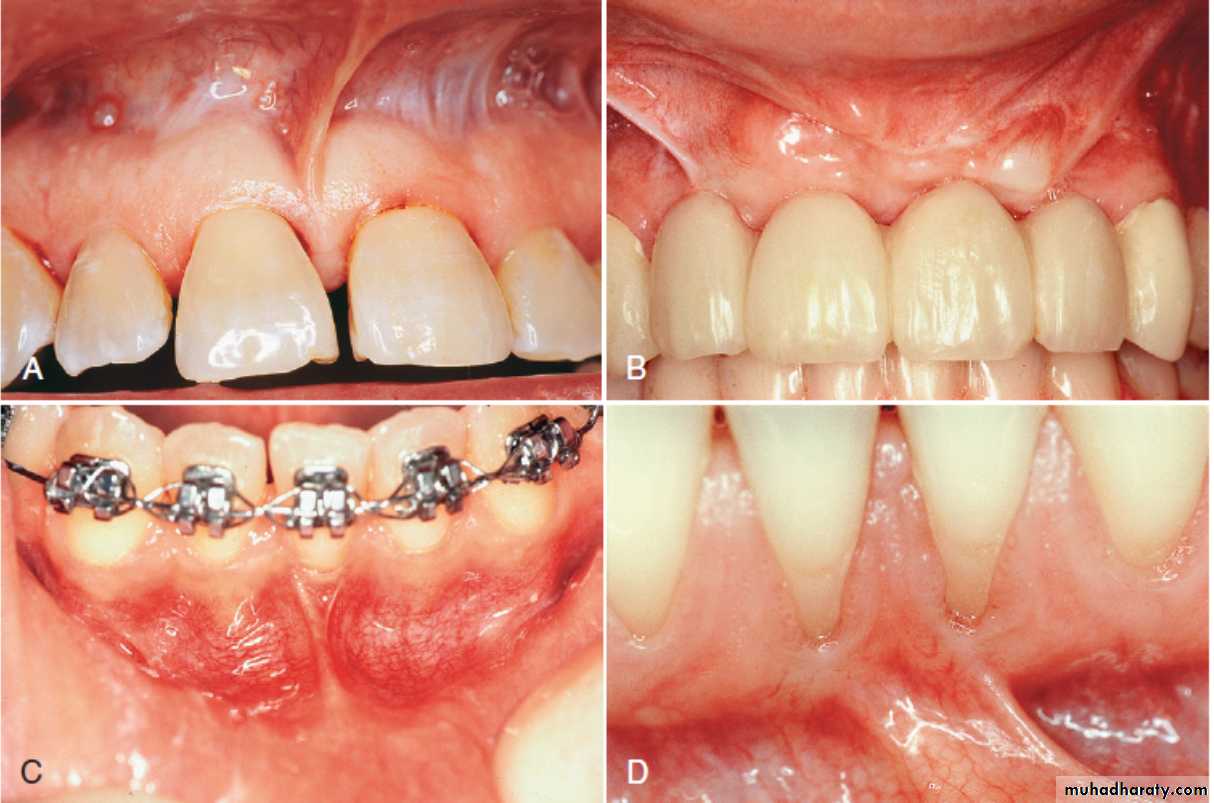

(A) Pretreatment recession defect of 3 mm to be treated with enamel matrix derivative (EMD). (B) Application of EMD to the root surface before coronally advancing the flap with 5-0 plain gut sutures. (C) The 1-year follow-up reveals 100% root coverage and increased keratinized gingiva.

Cell Therapy (Autologous fibroblast)(A) Preoperative view of the open interproximal space. (B) Four months after three injections into the papilla with the patient’s own expanded and concentrated fibroblasts, note the improved papillary form. Green horizontal lines are used for image analysis.